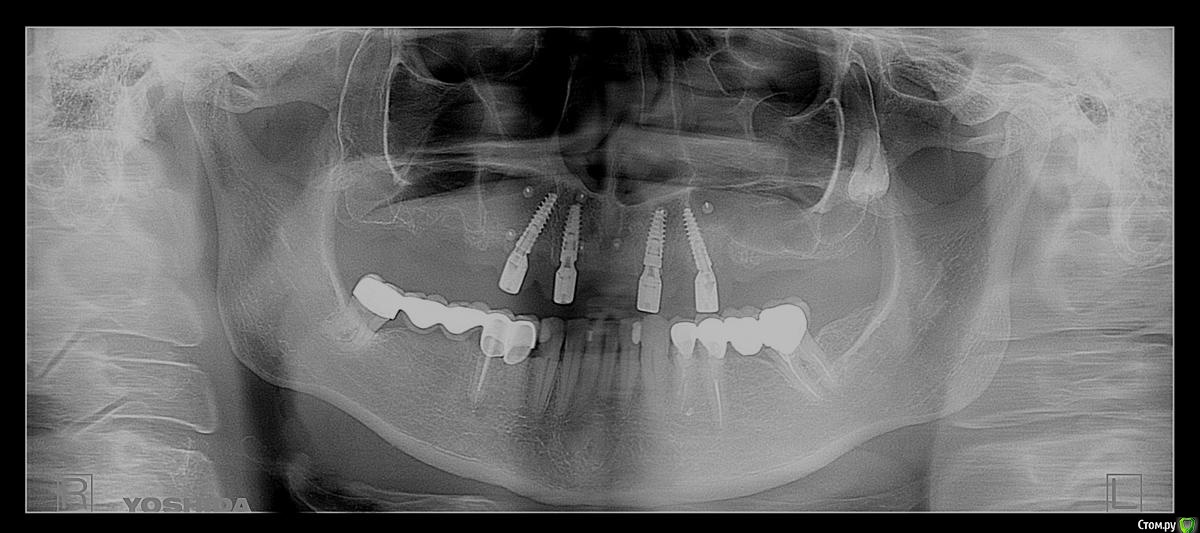

chervoncevdaniil Опубликовано 10 ноября, 2020 Поделиться Опубликовано 10 ноября, 2020 (изменено) Коллеги,есть пациент,внизу стоят коронки,установленные лет двадцать назад,пациент менять не хочет. На верху стоят 4 импланта,от съемного категорический отказ(неудачный опыт)Обсудили вариант с несъемной конструкцией с укороченным зубным рядом.(10 зубов)Вопросов несколько,какой материал бы вы предложили,и что по длинне консоли для этой конструкции. P.S.Винтовой фиксации тут не будет,импланты установлены нет под оптимальными углами. Я рассматриваю 3 варианта:1)Циркон в полную анатомию на индивидуальных абатментах с наддесневым уступом+небольшие консоли2)Мк на титановых премилах+небольшие консоли3)Циркон в полную анатомию с титановой балкаой и консоли(такие конгструкции не разу не делал)Акрил не хочу,потому что внизу мк коронкуЯ конечно,больше всего к первому варианту склоняюсь,но знаю что на циркониевых больших работах могут быть проблемы с трещинами.В общем,жду ваших советов/рекомендаци Изменено 10 ноября, 2020 пользователем chervoncevdaniil Ссылка на комментарий

Bruks Опубликовано 11 ноября, 2020 Поделиться Опубликовано 11 ноября, 2020 (изменено) Я бы сделал выбор в пользу ZrO2 дуги с уровня мультов. По одной (можно по 1.5) консоли с каждой стороны В балке здесь не вижу смысла, так как нет больших промежутков между имплантатами. Если взять прочный циркон: 1000-1300МПа, то сколов не должно быть. У нас в клинике, кстати, был недавно похожий кейс. Тоже низ МК+свои зубы, а ВЧ - все на 4 Изменено 11 ноября, 2020 пользователем Bruks Ссылка на комментарий

annda Опубликовано 16 ноября, 2020 Поделиться Опубликовано 16 ноября, 2020 (изменено) Понятно. Просто первое ОПТГ производит впечатление, что места навалом.Вот что значит- лечить по снимкам) Изменено 16 ноября, 2020 пользователем annda Ссылка на комментарий